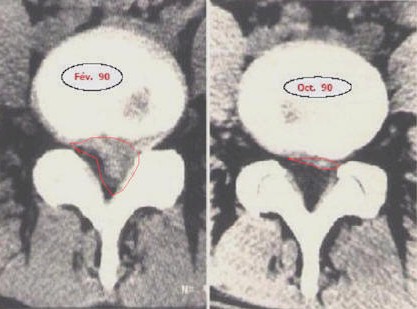

Figure 1 : Imagerie médicale montrant la régression de plus de 90% d’une hernie discale lombaire (entourée en rouge) sur une période de 8 mois.

Figure 2 : Résorption d’une hernie discale en 5 mois, SANS chirurgie.